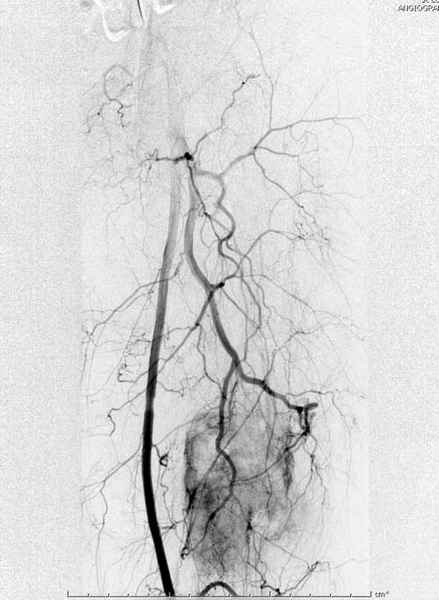

Для предупреждения кровотечения во время рассверливания, за день до операции провели эмболизацию сосудов питающий метастаз. http://radiology.rsnajnls.org/cgi/reprint/150/3/673.pdf (7-11, 12-15-16)